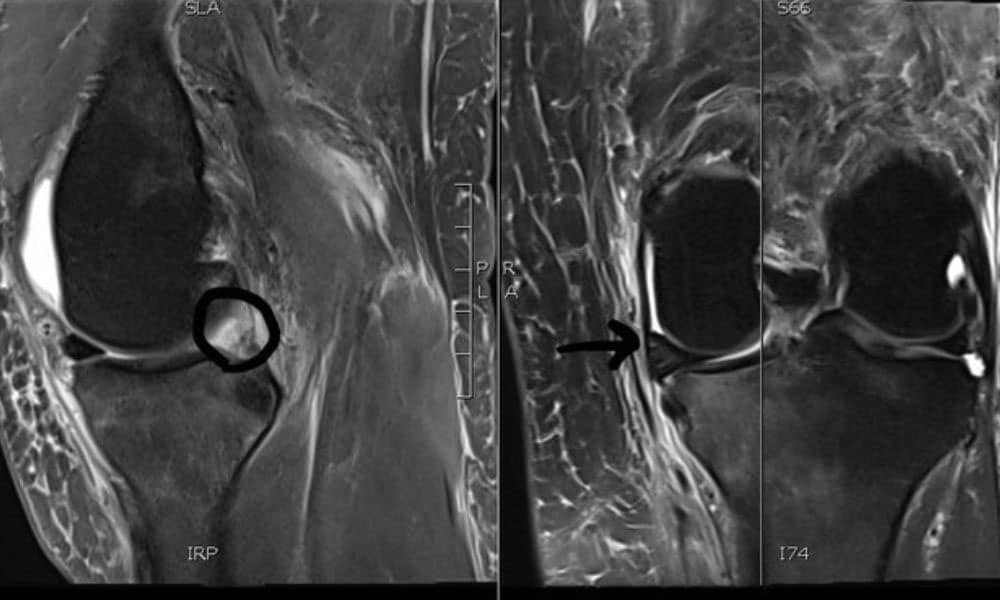

Here is a perfect example of the early sequelae of a medial meniscus root tear:

- The second group of patients who commonly tear their meniscal root is adults in their 50s. The consequences of a meniscal root tear appear to be much more severe in this age group. A meniscal root tear, which can occur with minor or seemingly trivial trauma, with a pop in the back of their knee with deep flexion, squatting and lifting, and other activities, can be quite severe. It is in this group of patients for which the rapid development of osteoarthritis can occur. In some of these patients, rather significant bone swelling, insufficiency fractures, and the appearance of osteonecrosis (avascular necrosis), can obscure one to seeing that it was caused by meniscal root tear.

Meniscal Root Tear Meniscal root tears can be seen on coronal, axial and sagittal MRI views. On the sagittal view, as seen in Figure C, there is a “ghost sign” which is indicative of meniscal root tear. A normal, healthy meniscus should look like a dark black triangle; however, as this figure shows the meniscus is much lighter or “ghosted” representing the root tear.